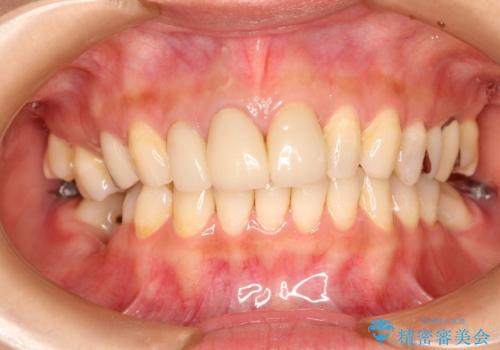

歯並びの改善とインプラントでのかみ合わせの回復 インプラント・セラミック・矯正全顎治療

- 歯医者が怖くて悪い歯をそのままにしてしまった、悪いところを治したいとのことで来院されました。

虫歯の歯や、歯を抜いてしまったところをそのまま放置していたことにより、歯並びも悪くなっていました。

矯正をはじめ、根の治療・インプラント・セラミックによる全体治療を提案させていただき、治療をしていくこととなりました。